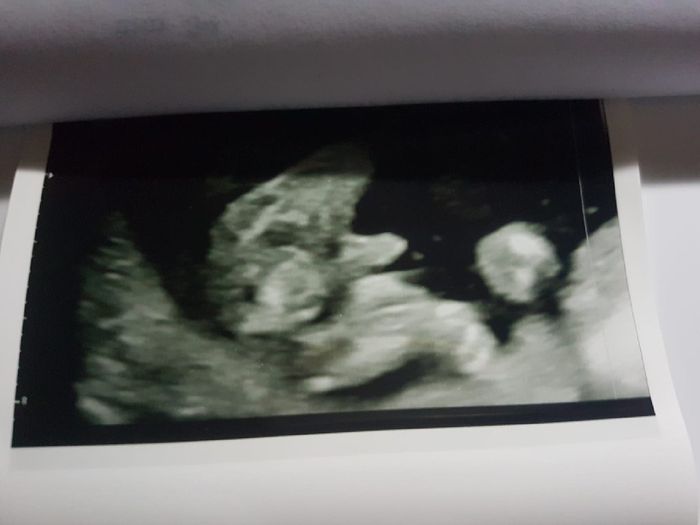

Ciao ragazze! Nell'attesa chi vuole giocare con me? Secondo voi è maschio o femmina? Fatta eco stamattina a 11+6! Io onestamente non saprei dire☺ ho letto la teoria Nub theory ma non riesco a interpretare la mia eco!